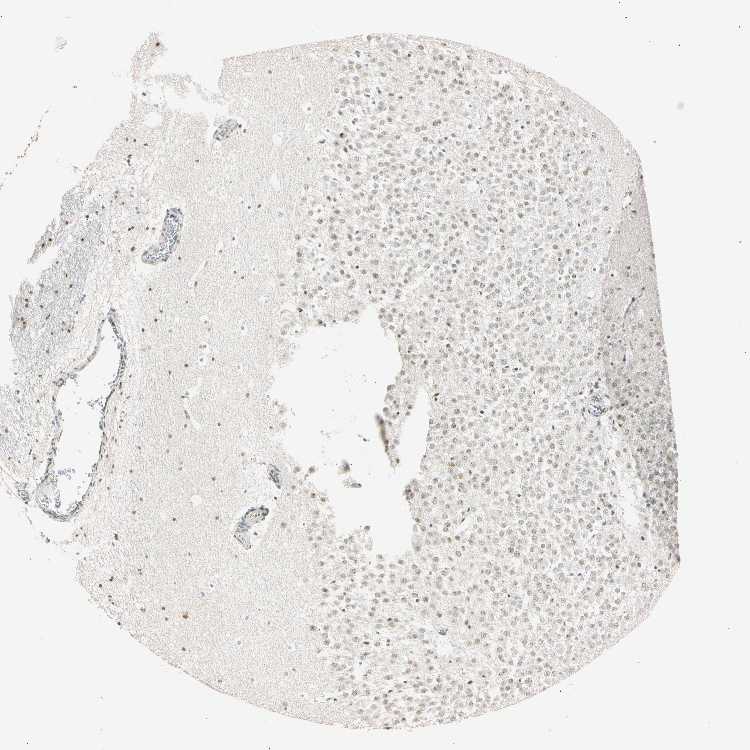

HIPPOCAMPUS - Antibody stainingi

Antibody staining in the annotated cell types in the current human tissue is reported as not detected, low, medium, or high, based on conventional immunohistochemistry profiling in selected tissues. This score is based on the combination of the staining intensity and fraction of stained cells.

Each image is clickable and will lead to virtual microscopy that enables deeper exploration of all samples and also displays staining intensity scores, fraction scores and subcellular localization as well as patient and tissue information for each sample.

Antibody HPA008751Antibody CAB005227

Glial cells MediumLow

Neuronal cells LowLow